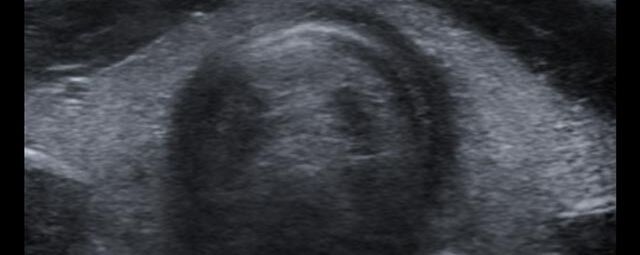

Die Sonographie ist ein bildgebendes Verfahren in der medizinischen Diagnostik, das mit Ultraschallwellen arbeitet. Ultraschall ist Schall mit einer Frequenz oberhalb der menschlichen Hörgrenze. Im medizinischen Bereich werden je nach Körperregion Ultraschallwellen in einem Frequenzbereich von ca. 3,5 – 18 Mhz verwendet. Die körpernahe Ultraschallsonde sendet durch einen piezoelektrischen Effekt kurze Schallwellenimpulse in den Körper. Ultraschall-Gel stellt den Kontakt zwischen Sonde und Körper her. Je nach Gewebeart werden diese Schallwellen im Körper unterschiedlich stark reflektiert. Anhand des zurückgesendeten Schallmusters kann das Ultraschallgerät Schnittbilder berechnen, auf denen die Organe des Körpers nach krankhaften Veränderungen untersucht werden können.

Der Arzt bewegt den Schallkopf mit leichtem Druck in verschiedene Richtungen. Die zu untersuchenden Strukturen können somit aus verschiedenen Perspektiven betrachtet werden. Aussagekräftige Bilder werden festgehalten und digital archiviert, Strukturen oder Organe können zusätzlich vermessen werden. Ein kurzes Befundgespräch erfolgt direkt nach der Untersuchung. Ihr zuweisender Arzt erhält von uns schriftlich einen ausführlichen Befundbericht.